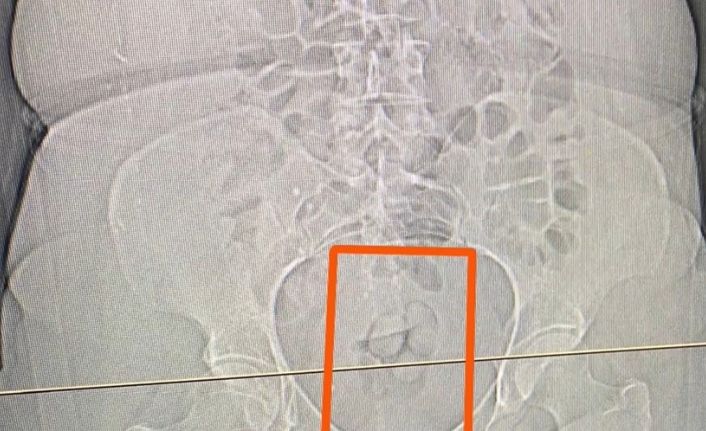

S.S. isimli şahısın şüpheli görülmesi üzerine çekilen tomografi neticesinde şahsın midesinde yabancı maddeler tespit edildi. Yapılan iç beden muayenesi sonucunda ise şahıstan 21,39 gram metamfetamin maddesi ele geçirildi.